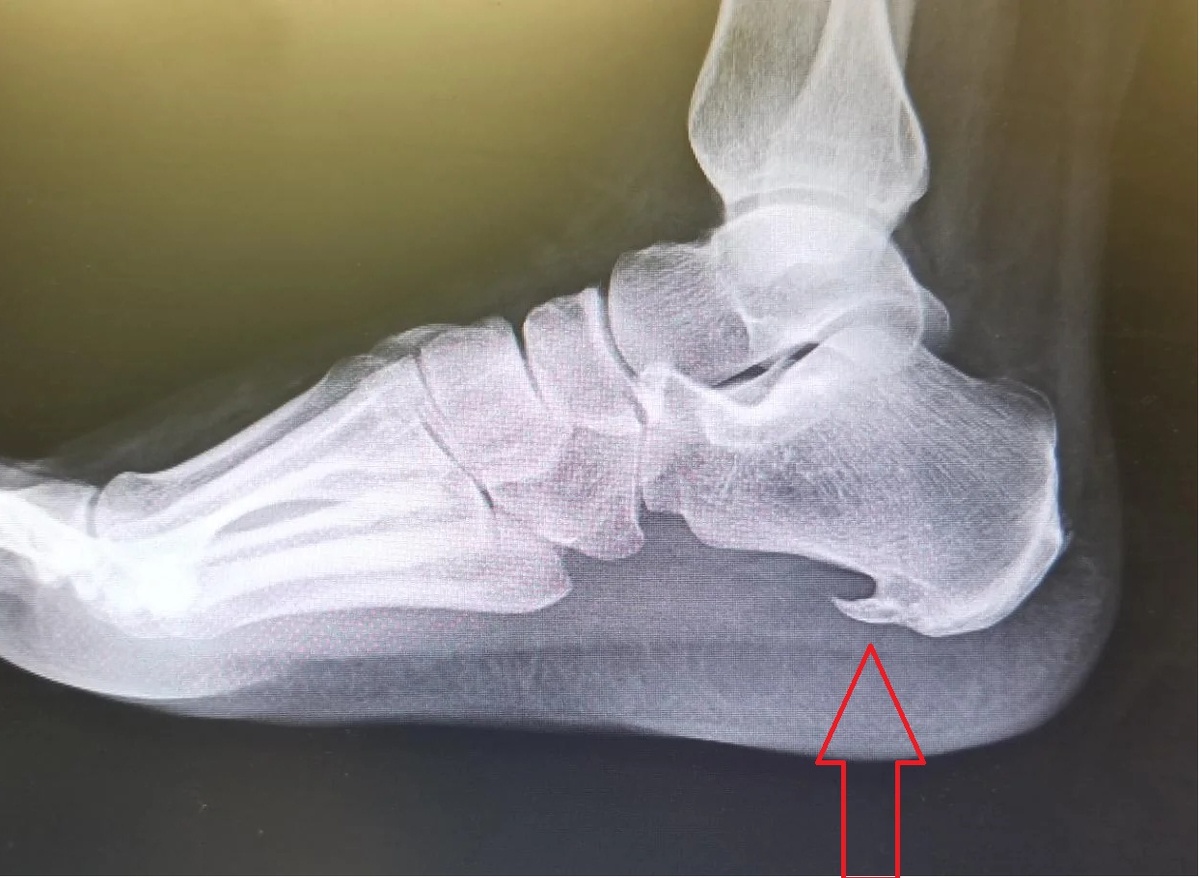

Пяточная шпора — это нарост из кальциевых отложений на нижней части пяточной кости. Он образуется в результате длительного воспаления подошвенного сухожилия – плантарной фасции. Костный выступ растет медленно. Первым признаком пяточной шпоры является дискомфорт в стопе, постепенно переходящий в боль. Сначала болезненность возникает только в утренние часы или после длительной ходьбы, но со временем проблема нарастает. С течением времени боль становится такой сильной, что человек может вообще утратить способность ходить.

Костный нарост в районе соединения пятки и плантарного сухожилия. Именно он вызывает боль при ходьбе.